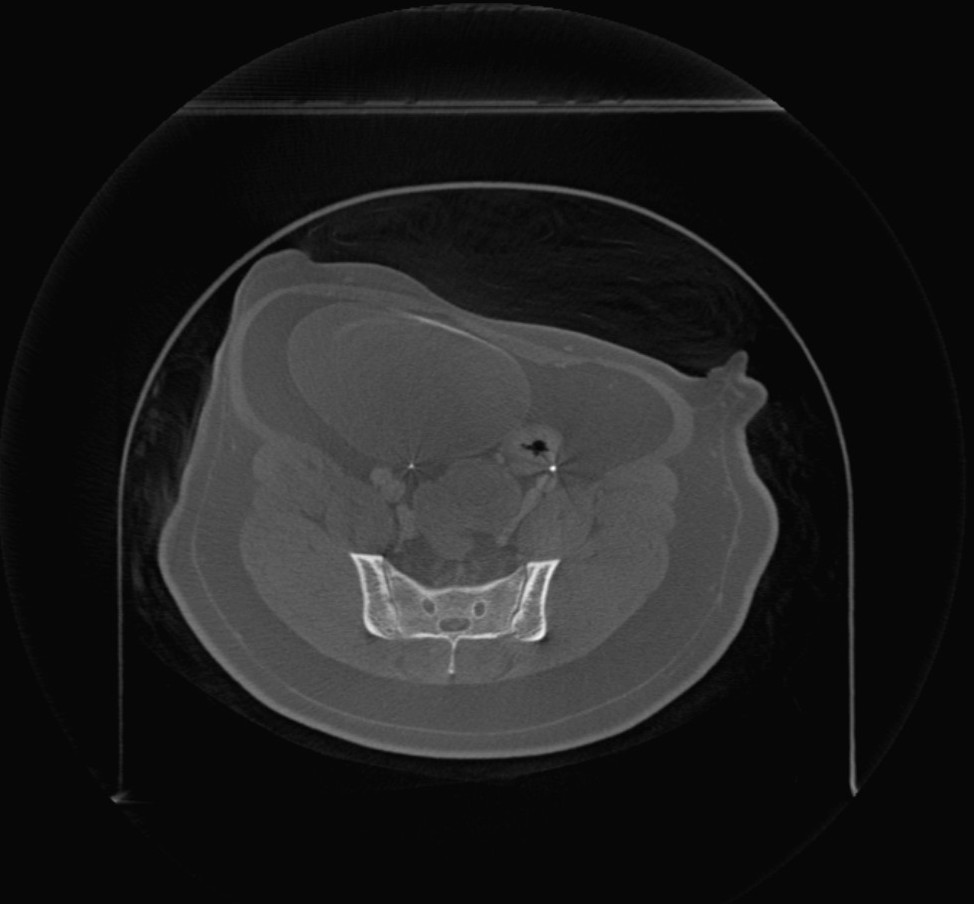

When opening volumetric DICOM images in the Viewer (CT and MR modality), an additional menu is available in the top toolbar titled Image Planes. Change the orientation of the image by choosing one of three available planes (Axial, Coronal,

and Sagittal).

The chosen plane affects the position and orientation of the CT/MR slices and their reconstruction on the 2D plane.